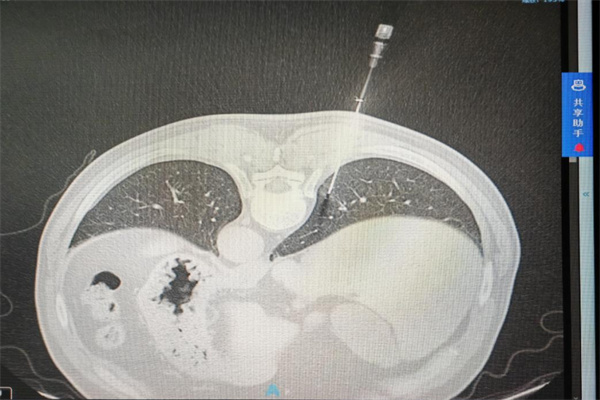

手术过程中,在局部麻醉后,刘前桂主任医师与程刚主任医师、田蓉副主任医师密切协作,先以粗针破皮建立通道,将同轴针精准插入胸膜腔,经CT再次确认进针方向无误后,稳步推进至病灶位置,顺利完成3针穿刺取样。

整个手术过程平稳有序,患者全程无明显不适。术后复查胸部CT显示,患者无气胸、出血等并发症,恢复情况良好,已顺利结束诊疗。此次穿刺获取的标本将为病理诊断提供可靠依据,为雷先生后续治疗方案的制定指明方向。